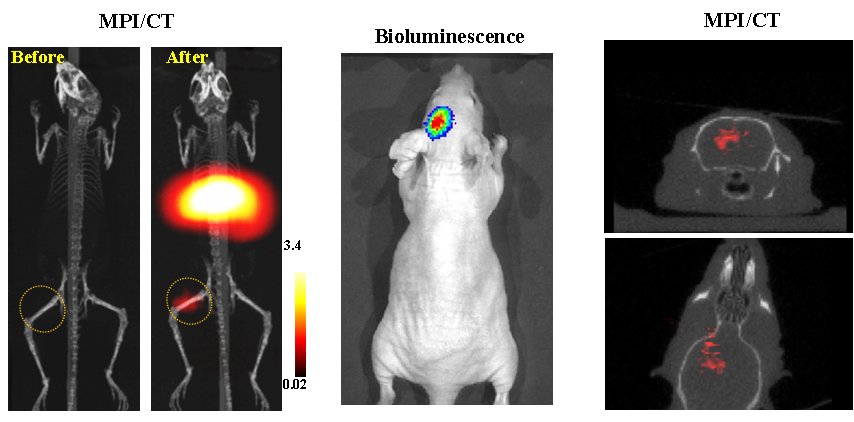

今年二月份,宋國(guó)勝教授與斯坦福大學(xué)饒江宏教授合作,通過(guò)系統(tǒng)的研究獲得了影響磁性粒子成像信號(hào)的作用規(guī)律和關(guān)鍵原理,開(kāi)發(fā)了新型磁性粒子探針---FeCo合金粒子,并首次應(yīng)用于磁性粒子成像(MPI)。該造影劑在極低含量時(shí)(5 ng)仍具有很強(qiáng)的造影效果。這意味著,未來(lái)在進(jìn)行人體成像時(shí),可以使用更小劑量的造影劑,從而避免高劑量造影劑引起的腎肝損傷?;贛PI的直接成像原理,我們可以對(duì)造影劑進(jìn)行正相和無(wú)背景干擾的活體成像,極大地提高信噪比。這項(xiàng)技術(shù)為腫瘤早期診斷、癌細(xì)胞示蹤、腦中風(fēng)、藥物輸送治療、肺部灌注成像、胃腸出血、神經(jīng)退行性疾病、磁熱治療等在活體中的可視化研究,提供了強(qiáng)有力的手段。相關(guān)研究成果以湖南大學(xué)為第一單位發(fā)表在Nature 子刊《Nature Biomedical Engineering》(IF = 18.952)。該期刊是“生物醫(yī)學(xué)工程”的頂級(jí)期刊。宋國(guó)勝教授為該論文的共同通訊作者。